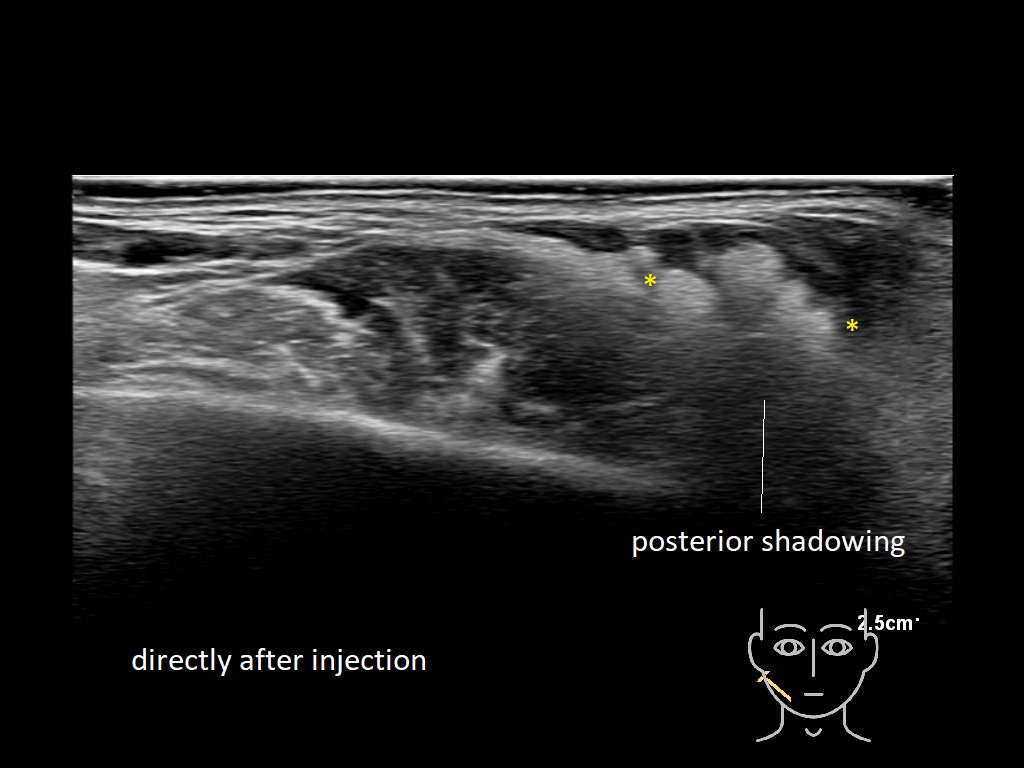

Fillers

Fillers

Filler library